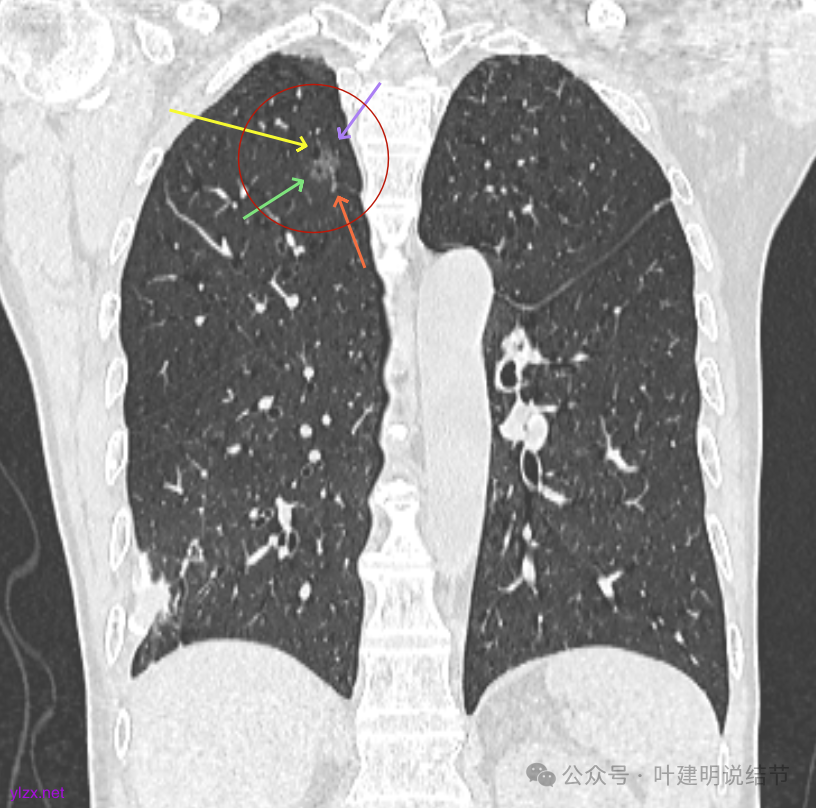

先看2020年9月的片子:

右上叶近脊柱旁有淡而纯的磨玻璃结节,整体轮廓与边界清楚,没有明显实性成分,也未见确切胸膜牵拉凹陷。

左上胸膜下有处偏长条小结节,也是磨玻璃密度的,轮廓较清。

左上叶前胸壁胸膜下有小结节,磨玻璃密度,有微小血管进入,轮廓与边界清。

右上冠状位显示病灶纯磨,血管进入穿行,灶内空泡征,表面毛刺征,没有明显实性成分。

左上病灶冠状位显示纯磨,部分连续细毛刺,灶内有扩张的细支气管似的,整体轮廓清。